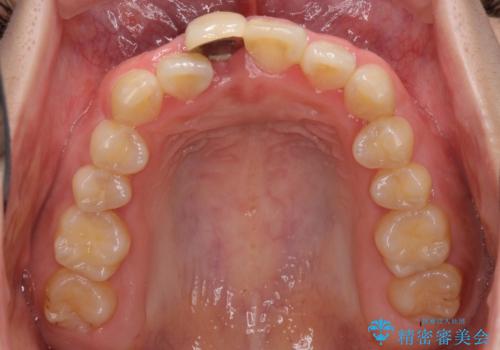

- 中学生の頃にぶつけた前歯に不格好なクラウンが装着されており、出っ歯な印象になっていることを気にして来院された患者様です。

ぶつけてしまった歯は保存が困難な状況であったので抜歯をし、ワイヤー矯正により歯列を整えつつ前歯の突出感を解消することとしました。

周りの歯にむし歯がないため、インプラントがお勧めとなりますが、事故による骨欠損が大きく、歯肉ラインを整えるのが困難という問題がありました。